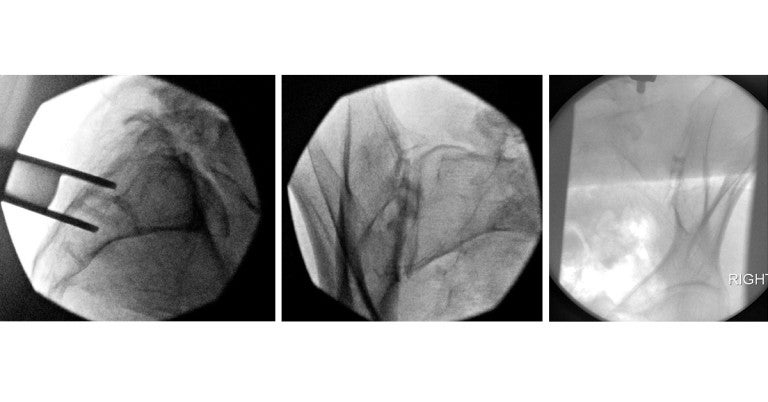

A novel approach to sacroiliac joint fusion is available at Lehigh Valley Health Network (LVHN) for people with sacroiliitis or sacroiliac joint dysfunction. The outpatient procedure involves inserting a small bone allograft into the joint using minimally invasive instrumentation, providing people with long-lasting benefits, quicker recovery and fewer complications than traditional sacroiliac joint fusion.

“Since I joined LVHN in 2020, my goal for the network has been to bring the latest minimally invasive spinal techniques and procedures to patients,” says interventional pain medicine physician Nirmal Shah, DO, who performed the first procedures for LVHN at Lehigh Valley Hospital (LVH)–Cedar Crest, LVH– Hecktown Oaks and LVH–Muhlenberg. “Patients today prefer surgeries with no overnight stays, quick recoveries and no long-term restrictions.”